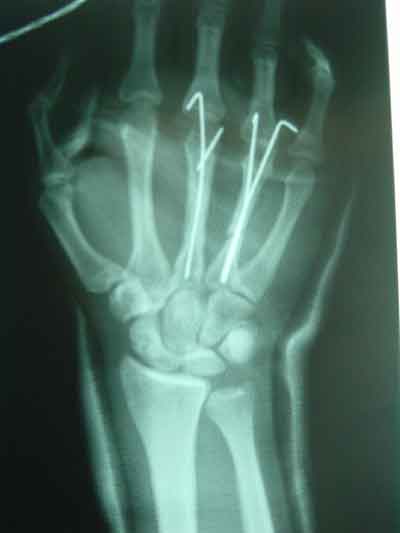

Bone Fracture And Healing System In Our Body